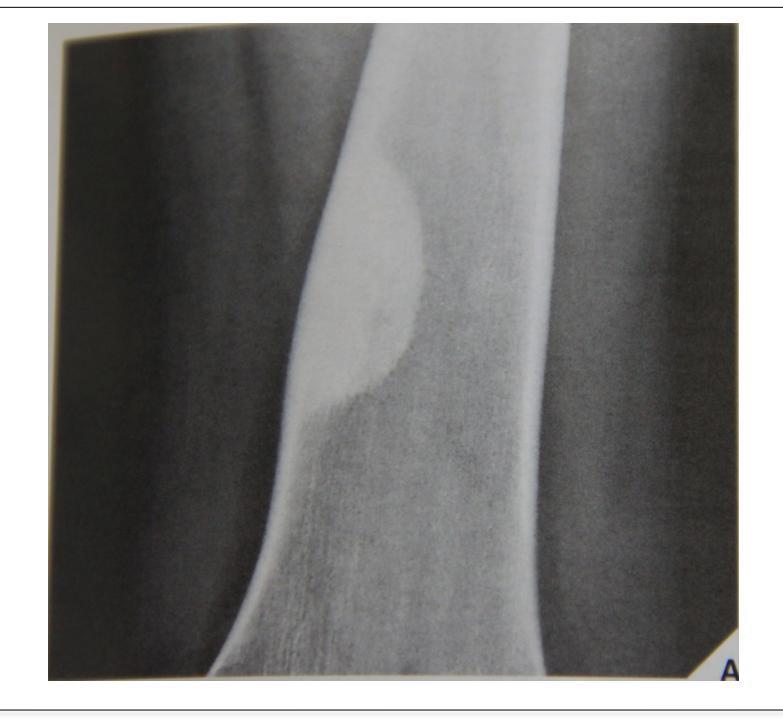

Non-ossifying Fibroma

site: Diaphyseal, metaphysal size: partial matrix: Mixed - Narrow zone of transition, well defined, syndosmosis soft tissue involvement: No tissue involvement